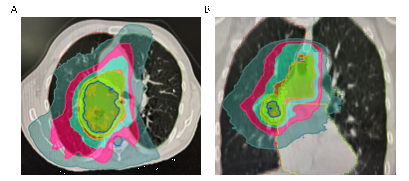

靶区勾画与放疗物理计划制定是精准放疗最为核心的步骤,该环节不需要患者的参与,但是需要患者的理解和配合。第一:放疗靶区勾画和物理计划制作非常复杂,需要反复优化,以达到最佳效果。放疗计划完成后,后续放疗没有特殊将完全按照该计划执行。所以该步骤需要一定的时间,需要病人耐心等待。第二:如图2所示,在照射肿瘤的同时(蓝线包绕区域),我们正常的肺组织、心脏、食管正常器官不可避免会受到一定的低剂量照射。这一点需要患者理解,最重要的是在治疗过程中,密切关注有无这些正常器官放射损伤相关症状。若有不适可以及时告知主管医生进行早期干预。

图2:肺癌放疗计划剂量分布图